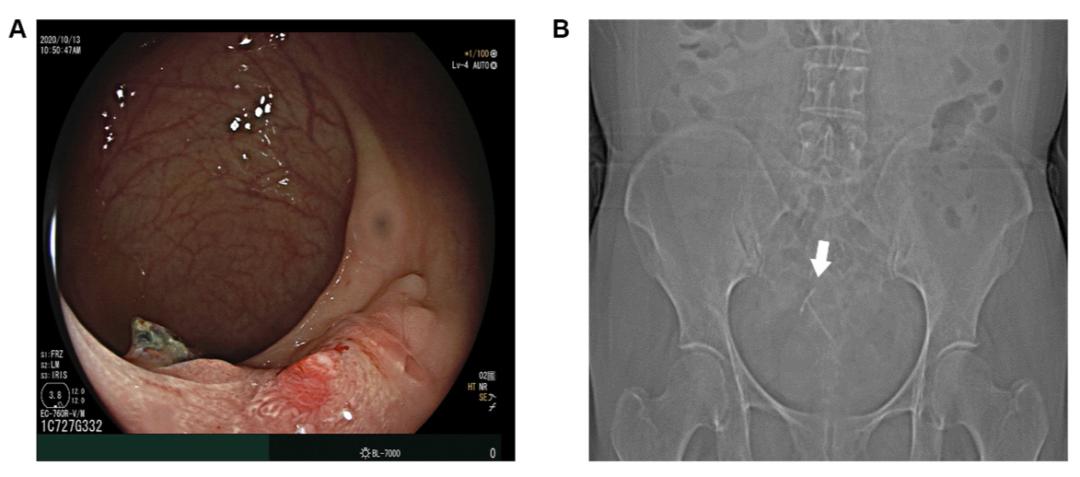

3.术前辅助检查

图1

图2